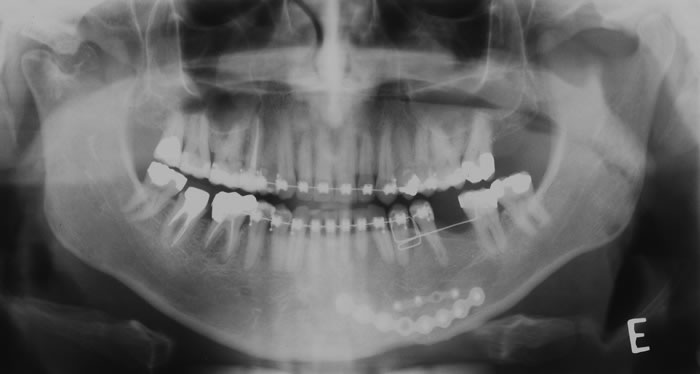

Nos softwares há ferramentas que permitem a reconstrução e a obtenção de novos cortes que mostram imagens de uso pontual na odontologia como os cortes transversais e longitudinais.

Os cortes transversais são cortes perpendiculares ao arco da maxila e mandíbula.

Na reconstrução panorâmica aparece uma régua no limite inferior que serve de localização para os cortes transversais.

Os cortes longitudinais são cortes no sentido vestíbulo lingual ou palatino, perpendiculares a uma reta traçada sobre o dente ou a área em questão.

1- A reconstrução panorâmica nada mais é que a representação em forma de panorâmica a partir de um arco criado sobre o rebordo, dessa forma, estruturas fora desses limites de reconstrução não aparecerão, diferente da radiografia panorâmica, onde estruturas “fora do foco” aparecem superpostas e por vezes borradas.